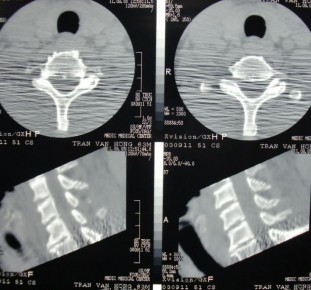

CT-scan, MRI cho biết có thoát vị đĩa đệm kèm theo hay không. Loại này gây tổn thương tủy là 50% [121].

X-quang cắt lớp điện toán tái tạo 3 chiều cho thấy rõ tổn thương.

Hình 1.29: X- quang cắt lớp điện toán CSC thấp.